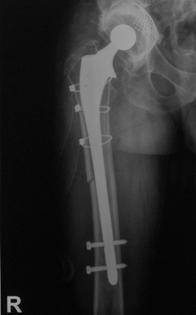

Proteza DLS.

Este o proteza din aliaj de titan, aluminiu si vanadiu (Ti6Al4V acoperita cu hidroxiapatita pe cea mai mare parte a lungimii sale, pentru a ajuta la fixarea ulterioara a protezei prin formarea de os la acest nivel.

Proteza prezinta o zona proximala rotunjita pentru o mai buna concordanta cu marele trohanter, un guler localizat medial pentru a marca nivelul penetrarii protezei in canalul femural, doua orificii localizate proximal in partea laterala a protezei pentru ancorare, un model asemanator solzilor de peste localizat anterior, posterior si medial pentru a ajuta osteointegrarea, un manson de hidroxiapatita ce se intinde pe doua treimi superioare ale protezei, treimea distala este neteda si lucioasa si este prevazuta cu doua orificii prin care se vor introduce suruburile de zavorare.

Privind din lateral proteza se poate observa forma anatomica a acesteia, proteza avand o dubla curbura pentru a se integra cat mai bine in canalul femural.

Suruburile de zavorare ce pot fi utilizate pot fi: cu fixare in corticala laterala, cu fixare in corticala mediala, cu fixare in ambele corticale. Dimensiunile suruburilor sunt intre 25 si 45 mm inclusiv, in incrementi de 5 mm.

Fig. Nr. 1.6. - Dimensiunile disponibile pentru protezele tip DLS[23]

Fig. Nr. 1.9. - Planificare preoperatorie - L - Lungimea protezei; Z - Zona de siguranta; F - Lungimea aripii protezei; C - Dimensiunea canalului femural la nivelul istmului; S - Dimensiunea protezei; D - Fosa digitala; SL1, SL2 - Suruburile de zavorare; OD - Diametrul cortical extern.

Planificarea preoperatorie este esentiala pentru ca interventia sa aiba un rezultat favorabil. Lungimea protezei se stabileste intraoperator, dar pentru o desfasurare optima a interventiei, trebuie sa fie disponibile toate lungimile si diametrele existente. Lungimea protezei (L) va fi astfel aleasa incat sa ramana o zona de corticala sanatoasa (Z) in lungime de minim 4 cm. Lungimea aripii protezei (F) se calculeaza de asemenea preoperator, ca si diametrul canalului femural (C) la nivelul istmului, iar pe baza dimensiunii canalului femural, tinand cont de necesitatea de a lasa 2 mm spatiu, se calculeaza dimensiunea protezei (S). Umarul protezei se va plasa la nivelul fosei digitale (D). SL1 si SL2 reprezinta suruburile de zavorare, ale caror lungimi se vor calcula in functie de diametrul cortical extern (OD).

Trei din cele 38 de solduri investigate au prezentat ca indicatie operatorie fractura periprotetica, doua solduri fiind diagnosticate cu fractura Vancouver B3, iar unul cu fractura Vancouver B2. Fracturile Vancouver B3 au fost tratate in ambele cazuri prin extractia protezei si introducerea unei proteze tip DLS de 275 mm lungime impreuna cu solidarizarea ansamlului folosind cate o placa si 4 cabluri in fiecare caz. Fractura Vancouver B2 a fost tratata prin extractia protezei si inlocuirea acesteia cu o proteza tip Modular.